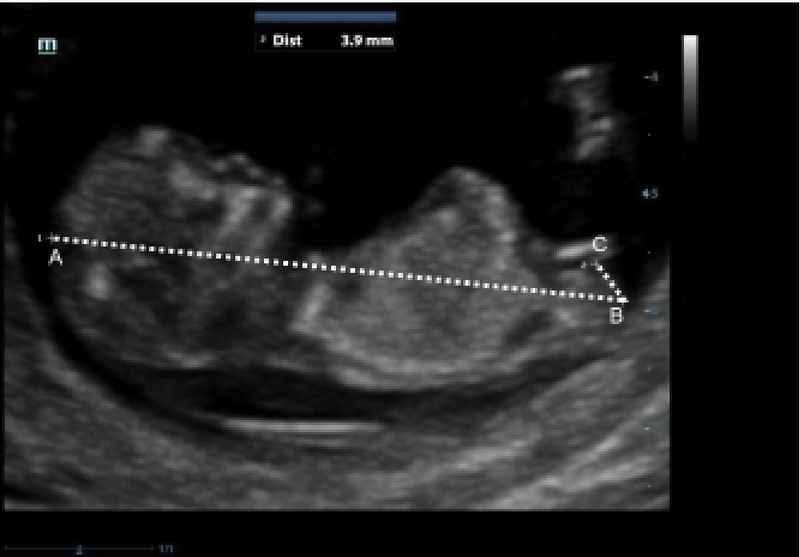

![Full text] Ultrasound measurement learning of fetal sex during the first trimeste | RRFU Full text] Ultrasound measurement learning of fetal sex during the first trimeste | RRFU](https://www.dovepress.com/cr_data/article_fulltext/s88000/88738/img/fig3.jpg)

Full text] Ultrasound measurement learning of fetal sex during the first trimeste | RRFU